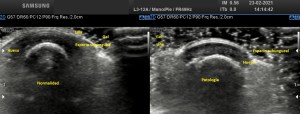

Cuando hice el corte longitudinal de la vesícula pude ver hasta tres patologías distintas, una adeomiomatosis (sin artefacto en cola de cometa), una litiasis vesicular y barro biliar, 2,3 y 4 respectivamente.

La adenomiomatosis, como un aumento de la ecogenicidad y el tamaño de la pared vesicular, la litiasis como una estructura hiperecogénica con sombra acústica posterior y el barro biliar, hiperecogénico rellenando toda la estructura ovoidea de la vesícula.

Para el estudio de la adenomiomatosis es obligado que el foco esté situado en la línea de interés, eso hará que las imágenes sean más nítidas y podamos estudiar dicha ecoarquitectura y su patología convenientemente.